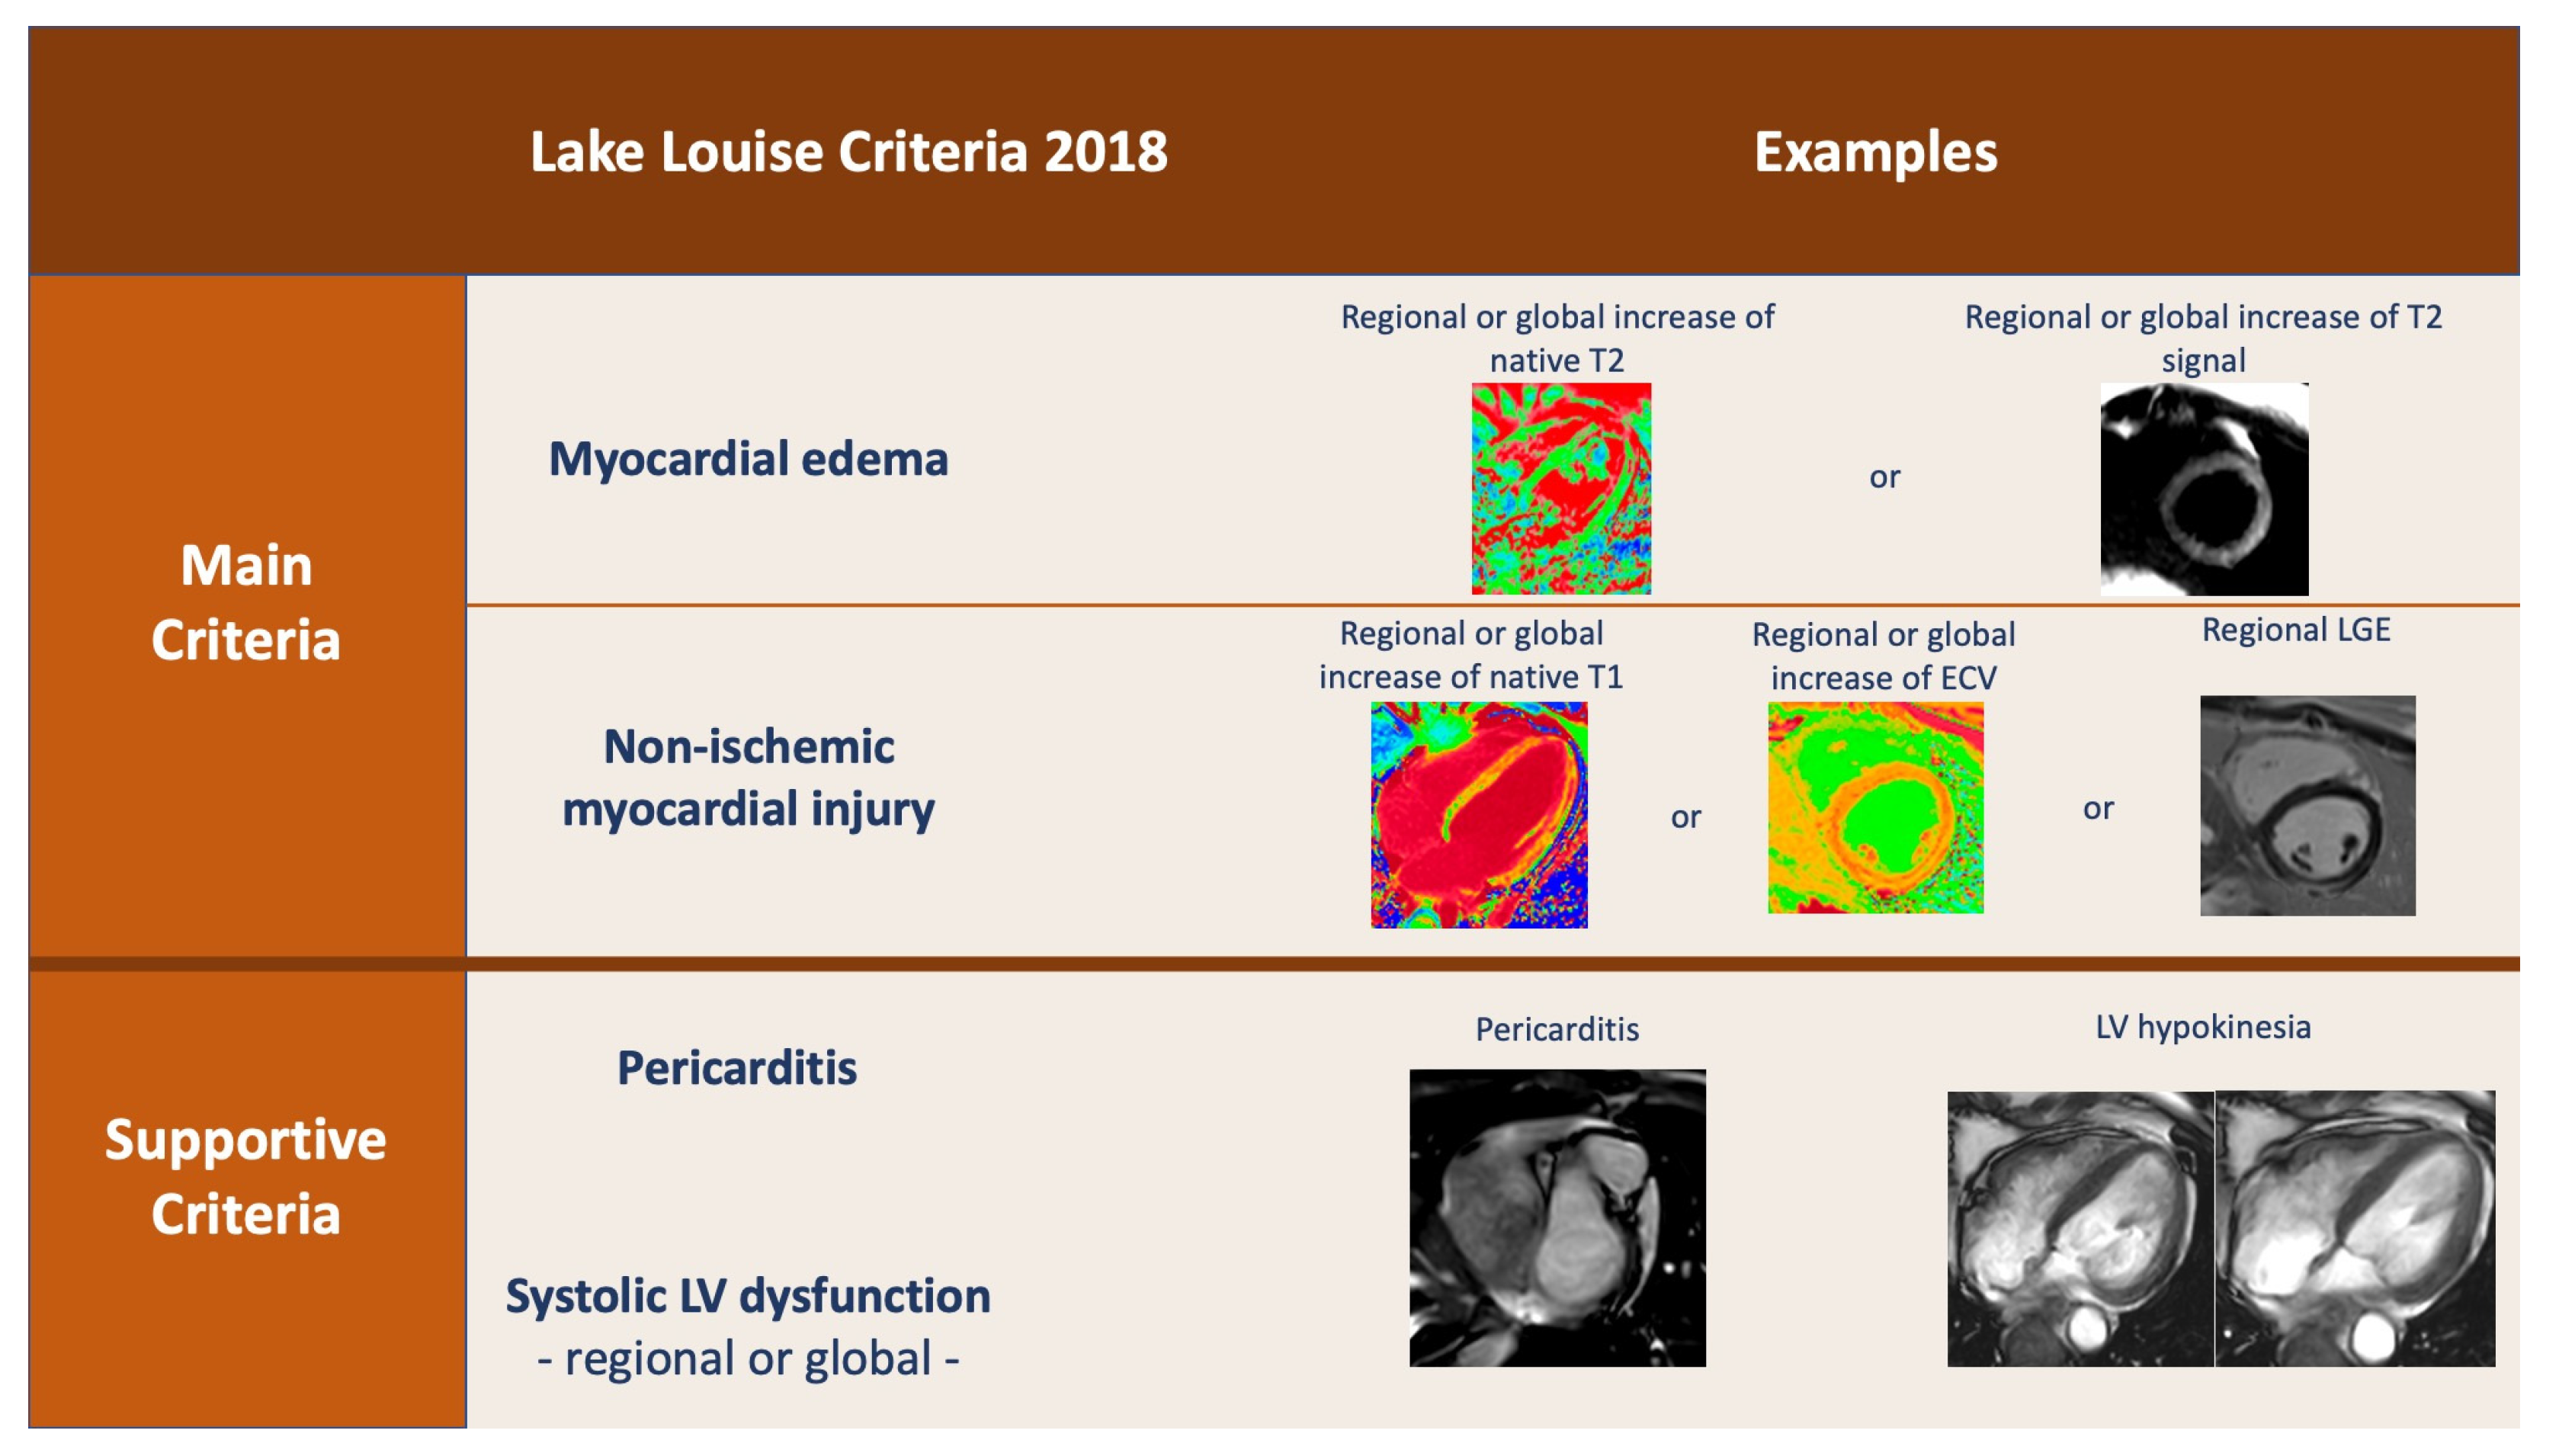

4. Cardiac Magnetic Resonance (CMR)

- Friedrich, M.G.; Marcotte, F. Cardiac magnetic resonance assessment of myocarditis. Circ. Cardiovasc. Imaging 2013, 6, 833–839. [Google Scholar] [CrossRef] [Green Version]

- Ferreira, V.M.; Schulz-Menger, J.; Holmvang, G.; Kramer, C.M.; Carbone, I.; Sechtem, U.; Kindermann, I.; Gutberlet, M.; Cooper, L.T.; Liu, P.; et al. Cardiovascular Magnetic Resonance in Nonischemic Myocardial Inflammation: Expert Recommendations. J. Am. Coll. Cardiol. 2018, 72, 3158–3176. [Google Scholar] [CrossRef] [PubMed]

- Kim, P.K.; Hong, Y.J.; Im, D.J.; Suh, Y.J.; Park, C.H.; Kim, J.Y.; Chang, S.; Lee, H.-J.; Hur, J.; Kim, Y.J.; et al. Myocardial T1 and T2 Mapping: Techniques and Clinical Applications. Korean J. Radiol. 2017, 18, 113. [Google Scholar] [CrossRef] [PubMed] [Green Version]

- Eitel, I.; Friedrich, M.G. T2-weighted cardiovascular magnetic resonance in acute cardiac disease. J. Cardiovasc. Magn. Reson. 2011, 13, 13. [Google Scholar] [CrossRef] [PubMed] [Green Version]

- O’Brien, A.T.; Gil, K.E.; Varghese, J.; Simonetti, O.P.; Zareba, K.M. T2 mapping in myocardial disease: A comprehensive review. J. Cardiovasc. Magn. Reson. 2022, 24, 33. [Google Scholar] [CrossRef] [PubMed]

- Georgiopoulos, G.; Figliozzi, S.; Sanguineti, F.; Aquaro, G.D.; Di Bella, G.; Stamatelopoulos, K.; Chiribiri, A.; Garot, J.; Masci, P.G.; Ismail, T.F. Prognostic Impact of Late Gadolinium Enhancement by Cardiovascular Magnetic Resonance in Myocarditis: A Systematic Review and Meta-Analysis. Circ. Cardiovasc. Imaging 2021, 14, E011492. [Google Scholar] [CrossRef]

- Haaf, P.; Garg, P.; Messroghli, D.R.; Broadbent, D.A.; Greenwood, J.P.; Plein, S. Cardiac T1 Mapping and Extracellular Volume (ECV) in clinical practice: A comprehensive review. J. Cardiovasc. Magn. Reson. 2017, 18, 89. [Google Scholar] [CrossRef] [Green Version]